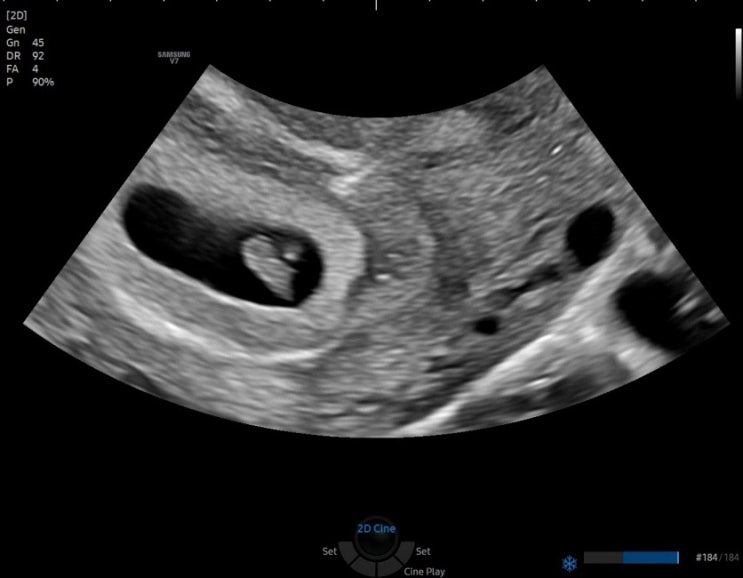

오늘은 제가 흥분된 마음으로 2024년 가장 특별하고 인상 깊었던 순간을 공유해볼까해요. 바로 임신 7주차...

8월 26일 띠용이 보러가는 날 설레는 마음으로 병원에 방문했다. 7주차라, 심장박동 소리를 들을 수 있다고...